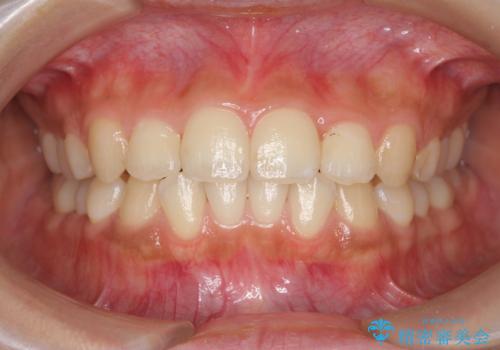

- 前歯のガタつき、上下たがい違いになっている歯並び(クロスバイト)の改善を求めて来院されました。

インビザラインによる矯正治療を行いますが、クロスバイトの改善をワイヤー部分矯正で事前に行うことにより治療期間の短縮する治療計画を立案します。

上下すれ違った噛み合わせはマウスピースでは改善に時間がかかり、またねじれが残ってしまうことも多々見られます。

マウスピース矯正を行う前に、これらの症状の改善の得意なワイヤー部分矯正を行うことで治療期間を短縮し、確実にすれ違いを改善することができます。